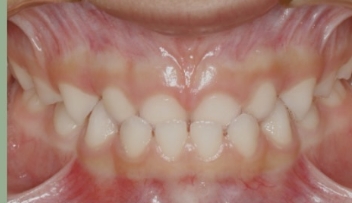

O tratamento que tem como objetivo tratar a má-oclusão através de recursos terapêuticos (aparelhos removíveis) que utilizam estímulos funcionais precocemente através de orientação mastigatória, desgaste seletivo, acréscimo às superfícies dentárias.